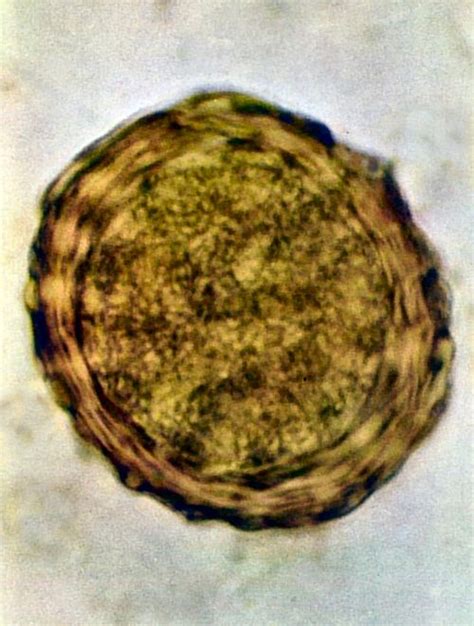

Kvasinková infekcia (Mykóza)

Kvasinková infekcia, známa aj ako vulvovaginálna kandidóza alebo mykóza, patrí k častým ochoreniam pošvy spôsobeným premnožením kvasiniek, najčastejšie Candida albicans. V gravidite sa vyskytuje častejšie, najmä v treťom trimestri, kvôli vyššej hladine hormónov, ktoré spôsobujú zvýšenie sladkého prostredia v pošve, čo je ideálne pre rast kvasiniek.

- Príznaky: Hustejší biely až belo-žltý výtok, tvarohový alebo syrový výtok, silné svrbenie, pichanie, pálenie, opuch a začervenanie genitálií. Môžu sa objaviť belavé povlaky medzi pyskami a bolesť počas pohlavného styku. Neskôr sa môže výtok sfarbiť do ružova v dôsledku narušenia slizničnej steny. Môže byť bez zápachu alebo s kyslým zápachom.